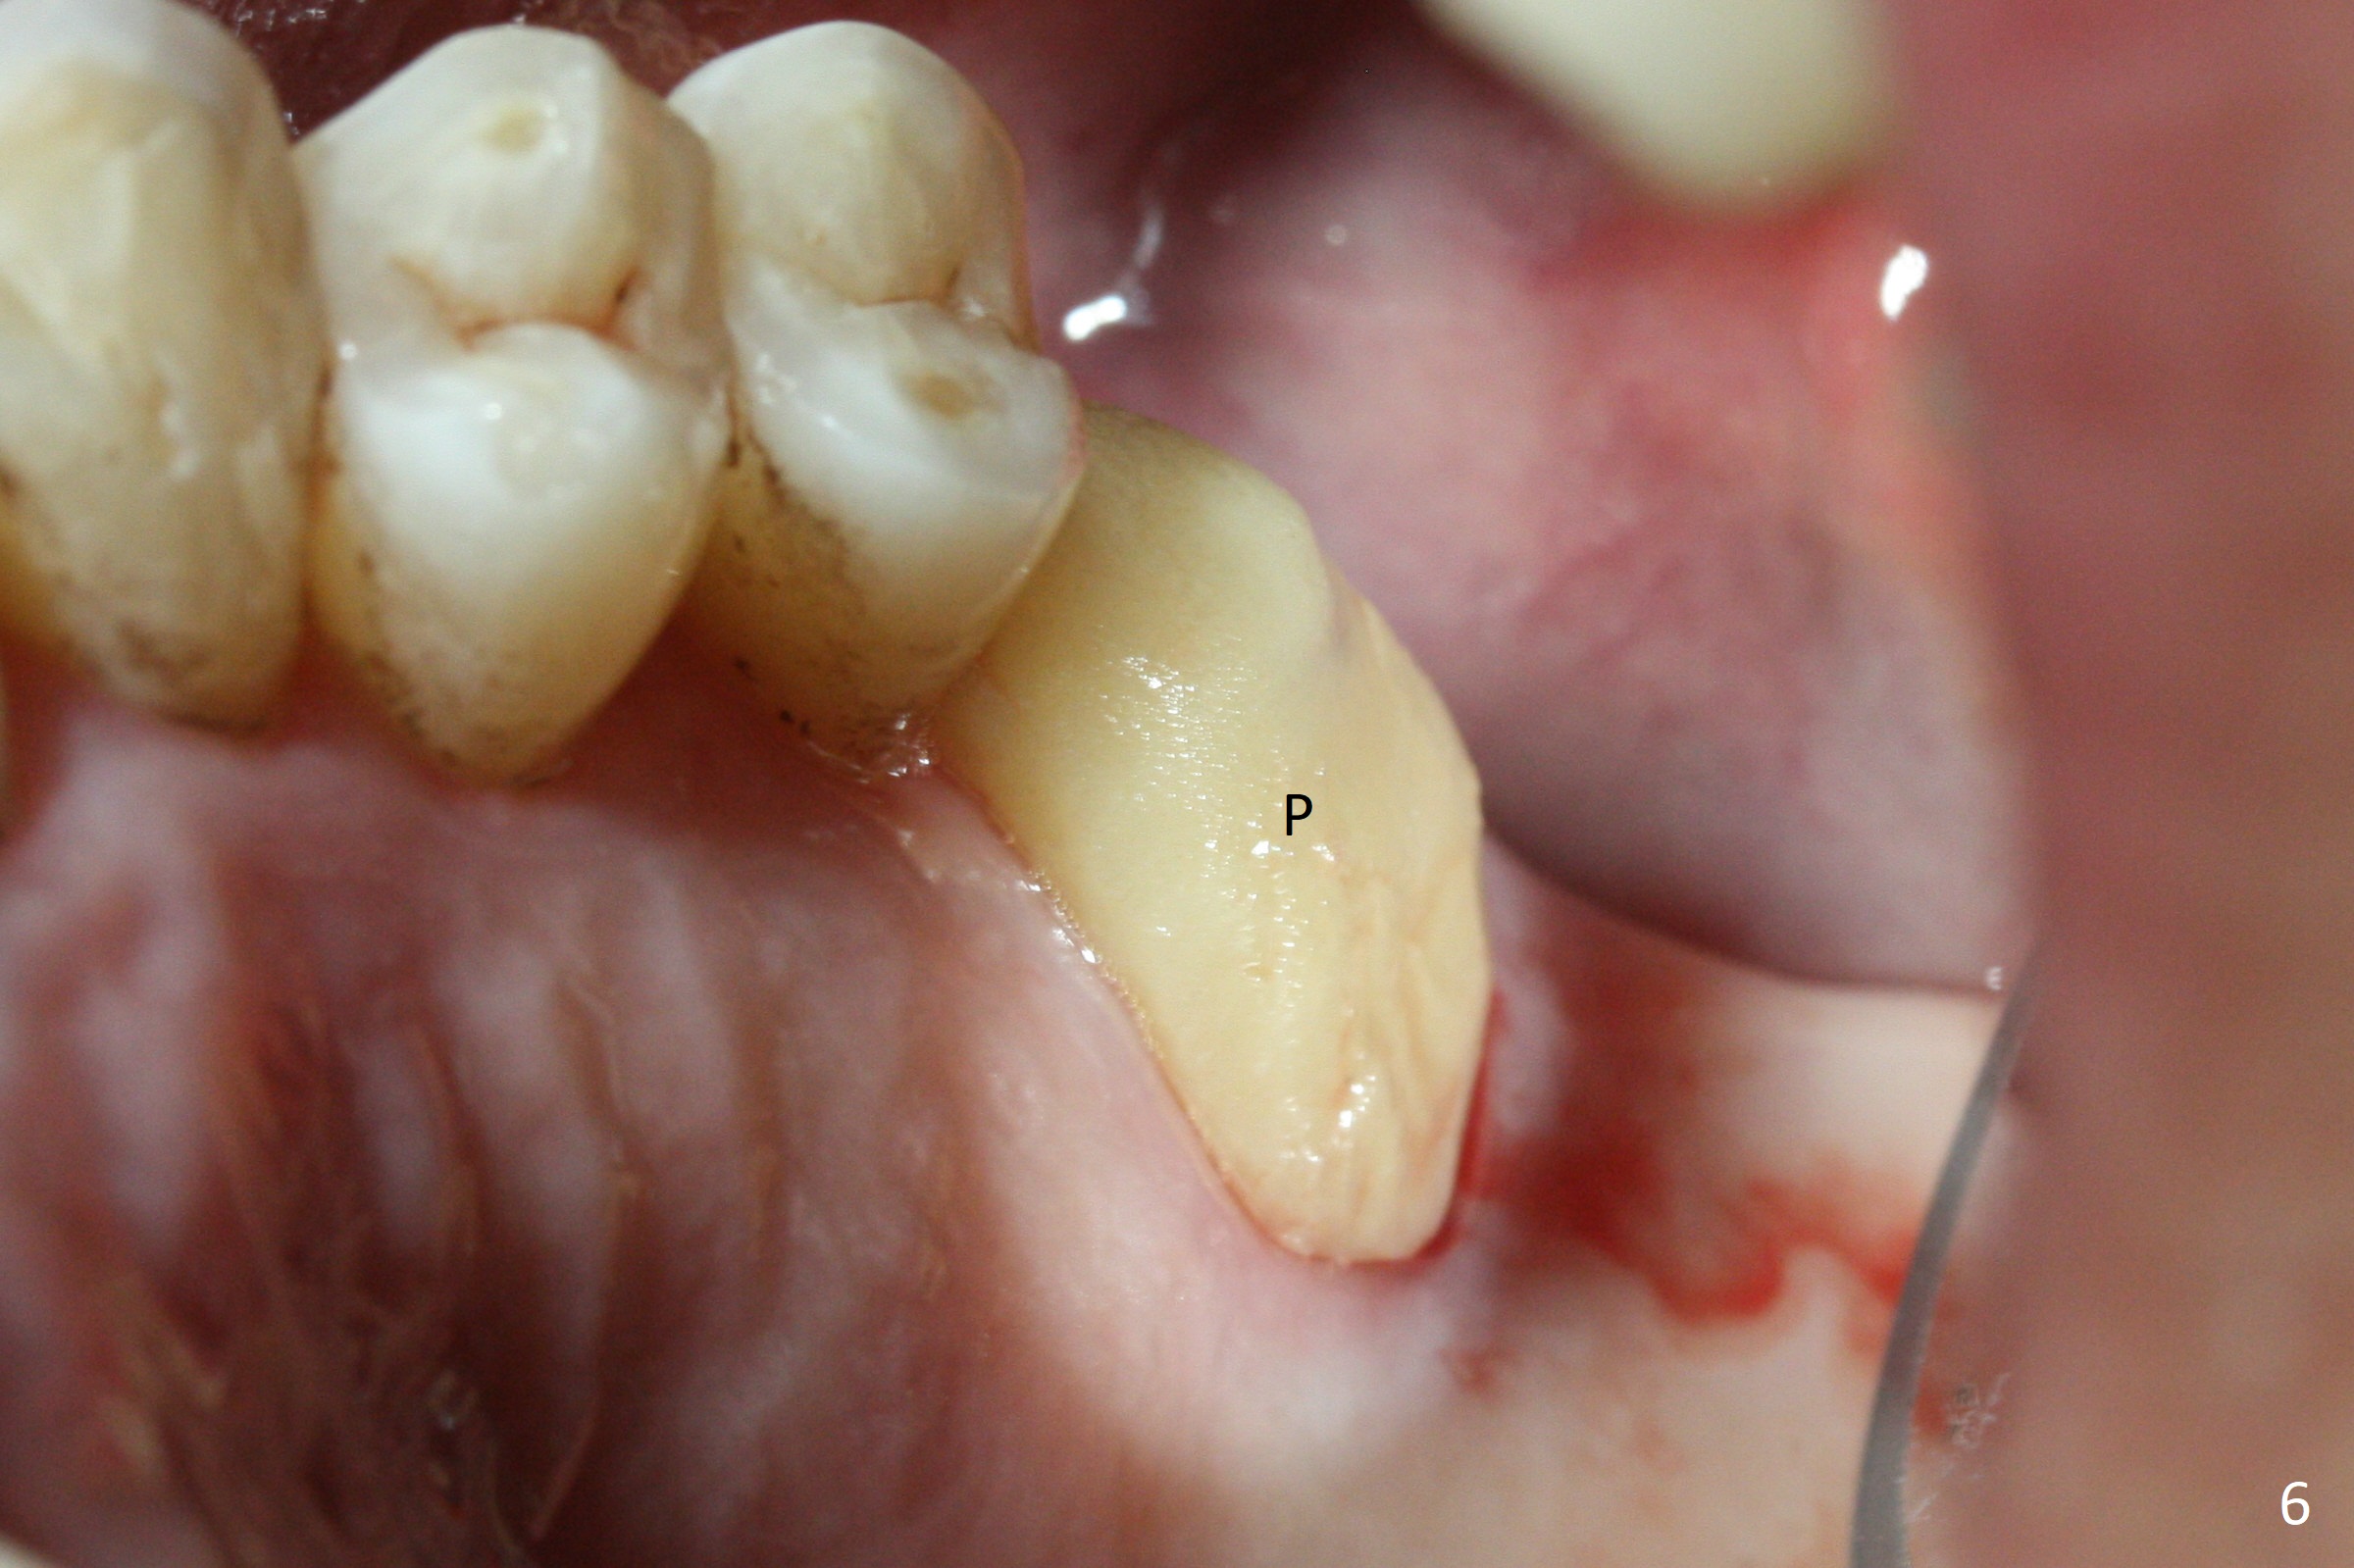

Buccal gingival recession at #14 (Fig.1) is less severe than the palatal one (Fig.2). Without raising the buccal gingiva (Fig.3 B), osteotomy in the septum is established apparently in the middle socket (Fig.3 *, 4). As the osteotomy increases with 3.8 mm drill, the palatal wall of the osteotomy starts to be perforating. When a 4.5x11.5 mm implant is placed, palatal threads are exposed, to which autogenous bone and Vera Graft are placed (Fig.5 *). After placement of a 5.5x5(3) mm abutment, an immediate provisional (Fig.6 P) is fabricated to cover the sockets. If the septal dimension were studied carefully by raising the buccal gingiva slightly, the osteotomy could be initially more buccal so that the palatal thread exposure could be less. When the provisional is removed 1.5 months postop, the implant is exposed palatally. The margin of the provisional is modified so that the implant can be cleaned by the patient using Water Pik. In fact, the healthy gingiva seems to be attached to the implant threads 2 weeks later (Fig.7). The distal implant threads remains exposed 6 months postop; it appears that the distal socket wall has resorbed (Fig.8). The sockets heal 1 year 7 months post cementation (Fig.9).